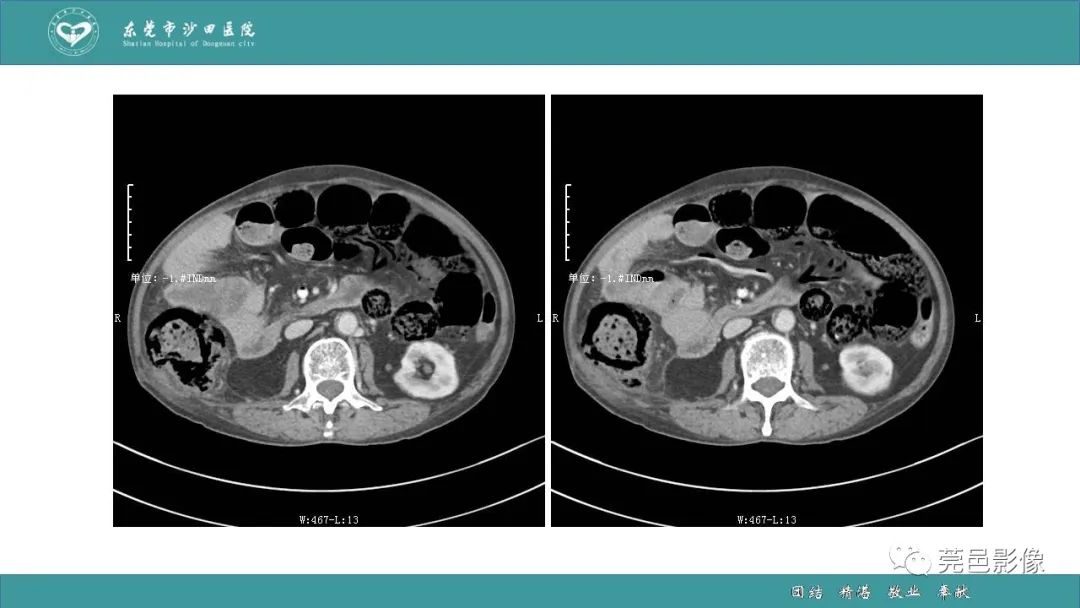

1例肠缺血坏死伴门静脉积气的CT诊断